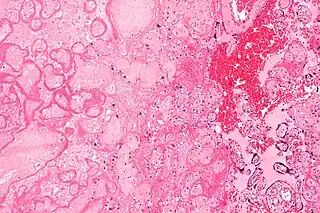

![]() Microfotografía de un infarto de la placenta (a la izquierda de la imagen), una causa de la hipoxia intrauterina. Tinción de H&E. | ||